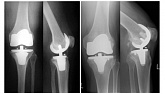

Endoprothetik des Kniegelenks

In den späten Stadien der Arthrose des Knies durch eine ausgeprägte Begrenzung der Bewegung begleitet, konstant starke Schmerzen, körperliche Unversehrtheit Verformung bis zur Genesung der einzige Weg ist der Ersatz des betroffenen Gelenks für eine künstliche - Endoprothetik.

Diese Methode ermöglicht es Ihnen, die richtige Form des Gliedes, eine vollständige Palette von Bewegung im Gelenke, zu entlasten ständige Schmerzen und Knirschen bei Bewegung und als Ergebnis wieder herzustellen, signifikant dem Patienten Lebensqualität zu verbessern.

Im Folgenden sind Röntgenaufnahmen und Fotografien, die die Strecke der Bewegung in der betroffenen Gelenke vor und nach der Operation veranschaulichen.